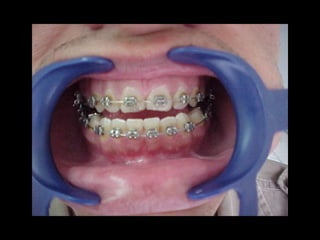

Eliminación de rotaciones.

Corrección de las discrepancias de longitud de arco.

Posición de los incisivos y molares por medio del

torque adecuado.

Llevar cualquier otra alineación en el arco.

Evita el potencial de recidiva

Aumenta la velocidad y eficacia del tratamiento

Eliminación de rotaciones. Correcciónde las discrepancias de longitud de arco. Posición de los incisivos y molares por medio del torque adecuado. Llevar cualquier otra alineación en el arco. Eliminación de rotaciones. Corrección de las discrepancias de longitud de arco. Posición de los incisivos y molares por medio del torque adecuado. Llevar cualquier otra alineación en el arco.

Evita el potencialde recidiva Aumenta la velocidad y eficacia del tratamiento